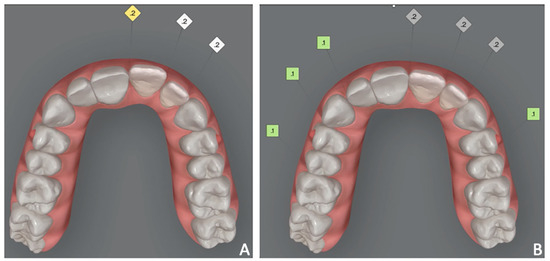

Figure 3. Case 1. Orthodontic set-up for staging movement for clear aligners therapy (Invisalign Go). (A) Pre-staged occlusal view; (B) post-staged occlusal view; (C) post-staged frontal view.

Orthodontic set-up. The Clincheck software (Invisalign GO) was used for evaluating dental occlusion and planning pre-prosthetic tooth movements (Figure 3). Afterward, the file of the final dental position was exported from the Invisalign GO digital platform. This file allows the dental technician to optimize the design of the veneers with reference to the final dental positions.

2.